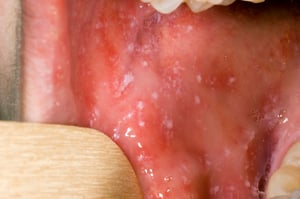

Các đốm Koplik ở niêm mạc miệng trông giống như những hạt cát trắng có quầng màu đỏ bao quanh. Các vết nội ban này là đặc trưng của bệnh và xuất hiện ở 70% số bệnh nhân (2). Các đốm Koplik xuất hiện trong giai đoạn tiền triệu trước khi xuất hiện nội ban, thường ở niêm mạc miệng đối diện với răng hàm trên thứ nhất và răng hàm trên thứ hai. Chúng có thể lan rộng, tạo ra đốm đỏ lan toả trong niêm mạc miệng.

Các đốm Koplik được mô tả một cách cổ điển là các đốm đỏ sáng với các trung tâm màu trắng hoặc hơi trắng có thể giống với các hạt cát. Chúng có thể xảy ra ở bất cứ nơi nào trong miệng, thường xảy ra trước khi xuất hiện triệu chứng và là đặc trưng bệnh lý đối với bệnh sởi (rubeola).

Hình ảnh từ Thư viện Hình ảnh Y tế Công cộng của Trung tâm Kiểm soát và Phòng ngừa Dịch bệnh.